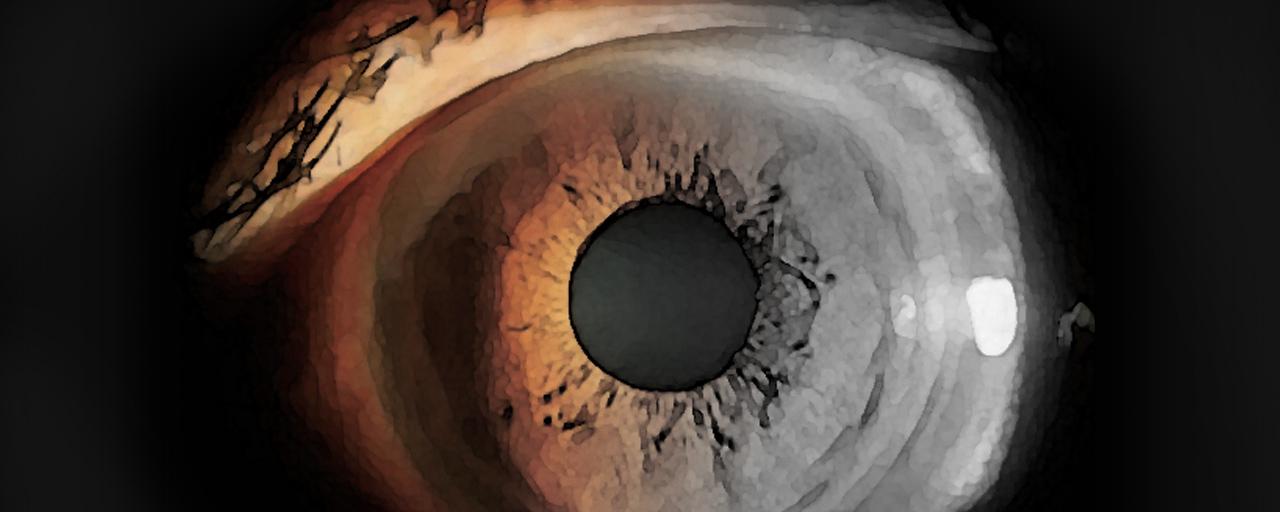

68歳の女性。5か月前からしばしば眼痛、虹視および軽度の頭痛を自覚しており、精査を希望して来院した。視力は右0.3(1.0×+2.5D)、左0.2(1.0×+3.0D)。眼圧は右19mmHg、左24mmHg。左眼の細隙灯顕微鏡写真を別に示す。